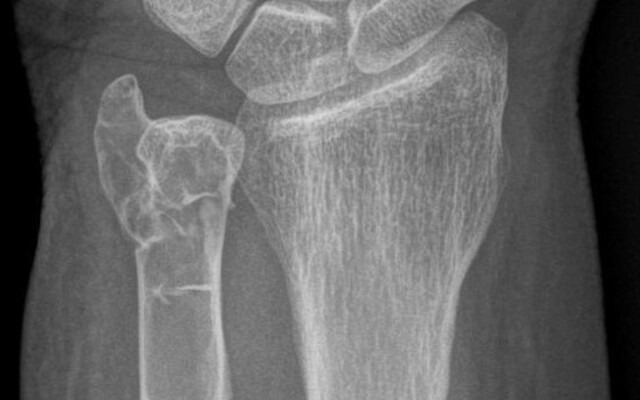

Een 63-jarige gezonde vrouw liep een polsfactuur op bij een struikelpartij. De fractuur bleek door een lytische botafwijking te lopen (figuur a). Vanwege het vermoeden van een maligniteit – zonder aanwijzingen hiervoor bij anamnese en lichamelijk onderzoek – werd een CT-scan van hals, thorax, abdomen en skelet uitgevoerd. Behalve de opzichzelfstaande lytische afwijking in de distale ulna links werden geen afwijkingen gezien. Het laboratoriumonderzoek was niet afwijkend, behalve een verhoogde gecorrigeerde calciumconcentratie en een verhoogde parathormoonspiegel, wat duidt op een primaire hyperparathyreoïdie. Een choline-PET-CT toonde een bijschildklieradenoom rechts caudaal. Het adenoom werd operatief verwijderd. Histopathologisch onderzoek liet geen aanwijzingen…